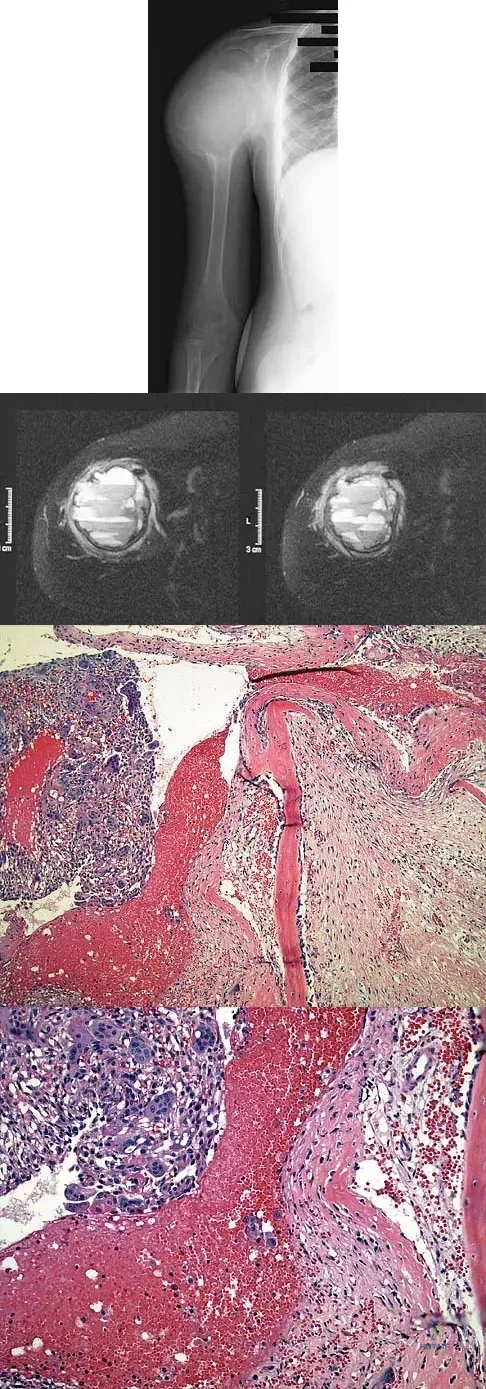

Question 24

A 15-year-old boy has had pain in the right shoulder for the past 3 months. He denies any history of trauma and has no constitutional symptoms. Examination reveals a large firm mass in the proximal arm. A radiograph and MRI scan are shown in Figures 27a and 27b. Biopsy specimens are shown in Figures 27c and 27d. Management should consist of

Explanation